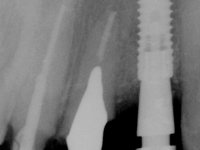

Endodontic treatments were performed and a metalic non screwed intra radicular post was placed on tooth 1.1. An alginate impression was made for laboratory confection of a reinforced acrylic provisional bridge, with teeth 1.1 and 2.2 as abutments and 2.2 as a pontic. After preparation of tooth 1.1 and root preparation of 2.1, the bridge was relined in mouth with self-polymerizable acrylic using a metal post for further retaining the prepared root canal on 2.1. Tooth 2.2 was cut at the gingival level to function as support. In the same session, the impression of the root canal of the 2.1 was made for the laboratory confection of a cast post and core. A double mixture technique with plastic tutor was used after previous canal vaseline with endodontic file and cotton. The provisional bridge was provisionally cemented and the cast post and core was made in the laboratory. Cast post and core cementation was made with resin-reinforced glass ionomer cement and the provisional bridge had to be readjusted to the new situation by removing the post at the site of 2.1. After careful surgical planning, a dental implant was placed, simultaneously with extraction of the root of tooth 2.2. The provisional bridge was placed by resting on the healing screw placed in the implant. The respected osteointegration period was 12 weeks, during which the provisional bridge was relined twice. After complete maturation of hard and soft tissues, definitive impressions were made. The gingival retraction technique was applied with an impregnated retraction cord and impression was performed using double mixture, open tray impression technique. A custom precious metal abutment implant was prepared in the lab, along with 3 metal caps to be used as infrastructures for the metal ceramic crowns. Particular care was taken in the confection of the cervical finishing line of the implant abutment, in order to follow the soft tissues emergence profile. Proof of infrastructures was done in the mouth being evaluated clinically and imagiologically. Collection of color information was done by the ceramist at the office. Ceramic was applied in the laboratory and the finished work was placed in the mouth after approval by the patient. Definitive cementation was made with resin-reinforced glass ionomer cement, and the first crown to be cemented was that of the implant, to facilitate removal of the excess.